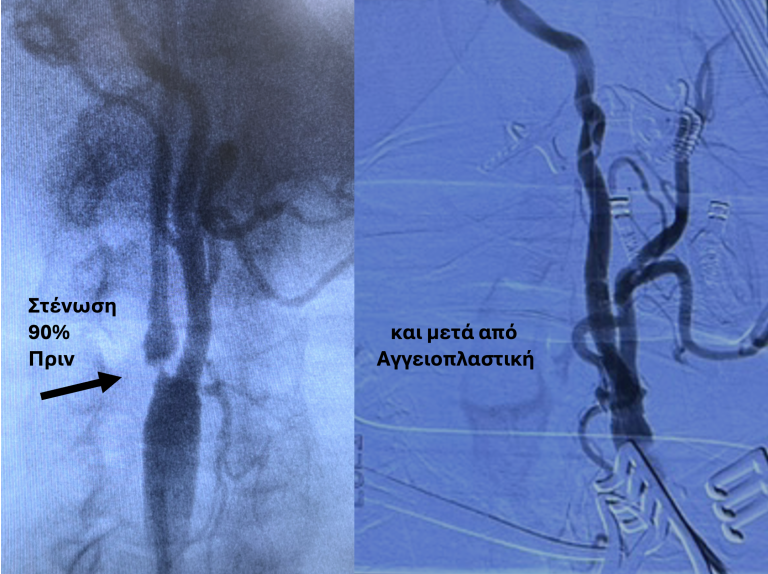

- Triplex κοιλιακής αορτής και λαγόνιων αρτηριών – Βοηθά στην έγκαιρη διάγνωση ανευρυσμάτων και στενώσεων που μπορεί να εξελιχθεί σε επικίνδυνες επιπλοκές.